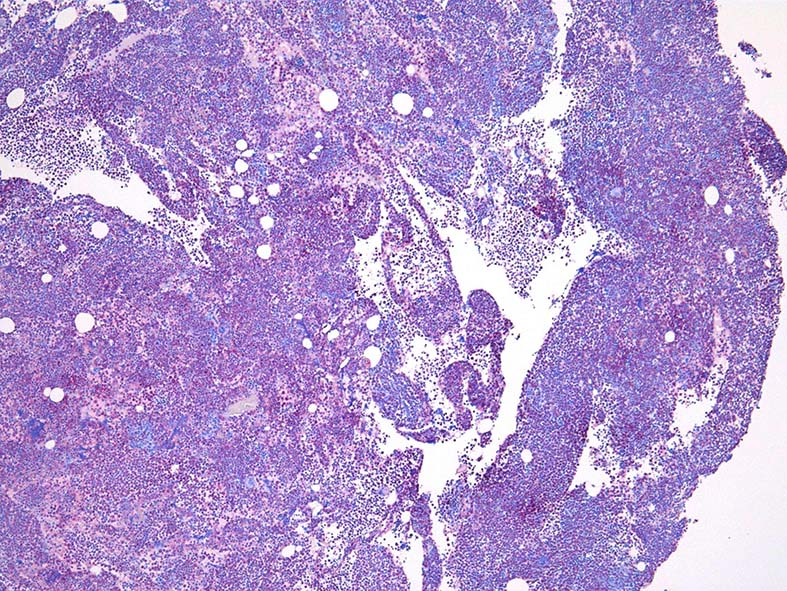

Naphtohl-ASD-CAE Fig.03

Fig.01: hypercellular marrow. ASDで赤染する細胞の増加=granulopoietic hyperplasiaがある.

Fig.03: granulopoietic hyperplasia. 成熟顆粒球の増加もある.